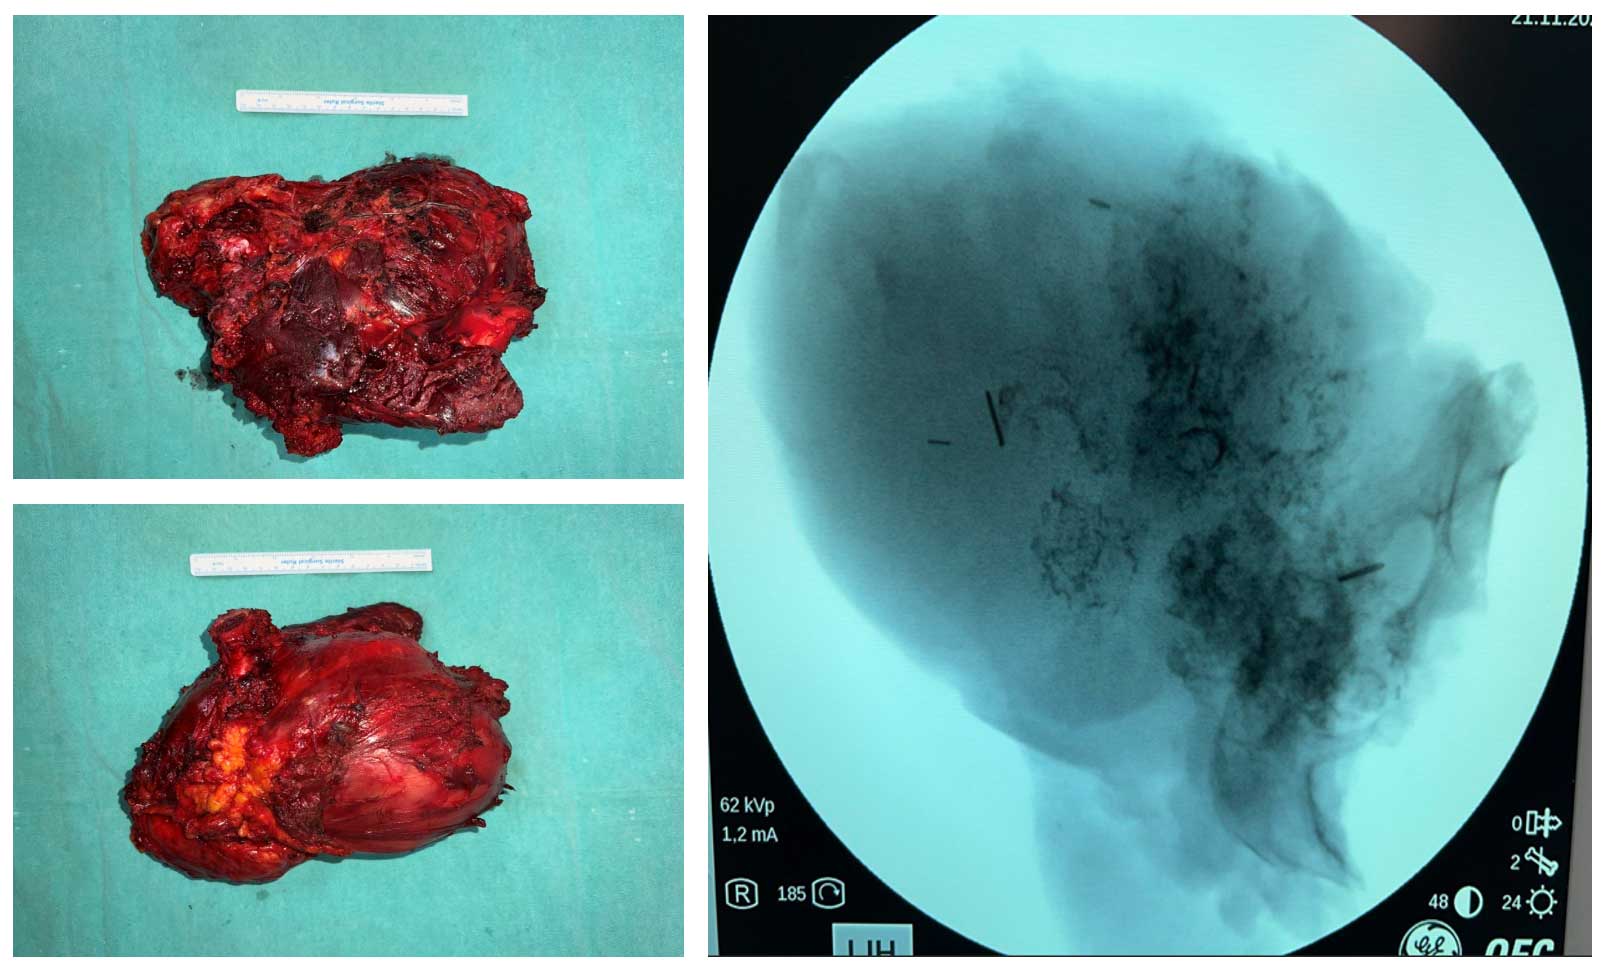

Ameliyat Esnası: Çıkarılan tümör dokusunun klinik ve skopi görüntüsü.